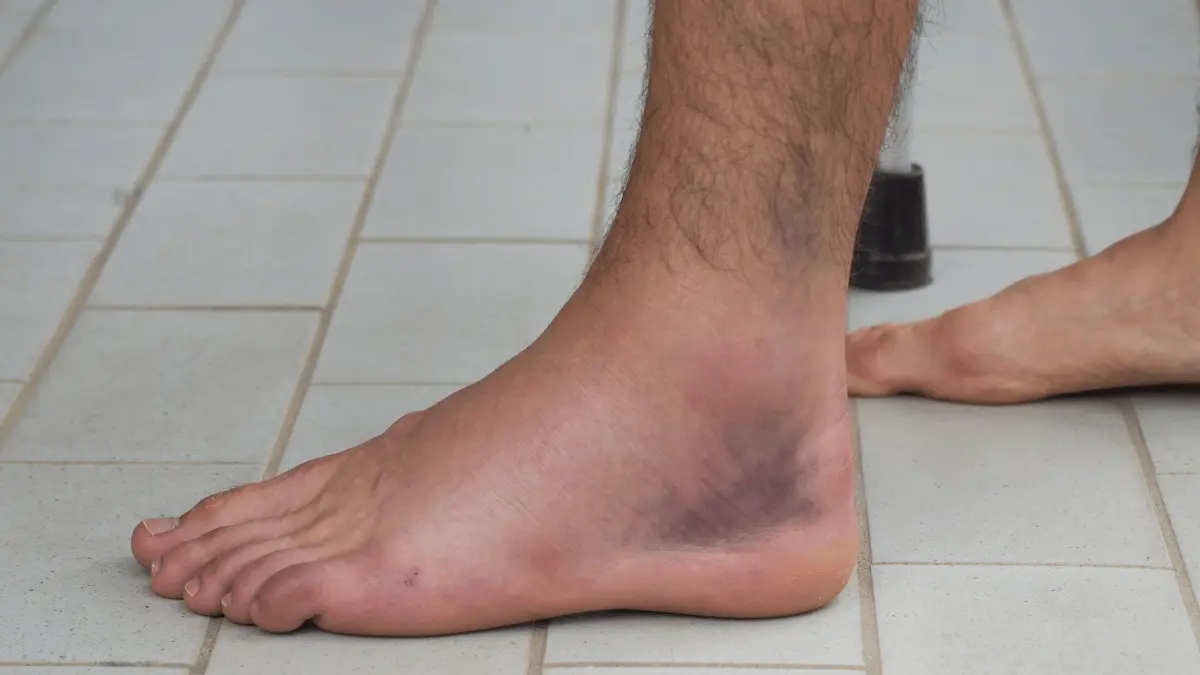

A instabilidade crônica do tornozelo ocorre quando os ligamentos laterais deixam de segurar a articulação com firmeza após entorses repetidas.

O paciente passa a sentir “falseios”, dor na borda externa e medo de torcer o pé em atividades simples.

Principais sintomas

Os sinais variam de “insegurança” subjetiva a entorses objetivas de repetição.

A dor costuma localizar-se na face lateral, com inchaço, rigidez matinal e dificuldade em terrenos irregulares. Em atletas, o desempenho cai por medo de torcer.